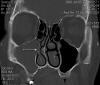

JFC Etmoiditis bilateral

JFC Sinusitis maxilar. Espolón septal.

JFC Sinusitis Maxilar